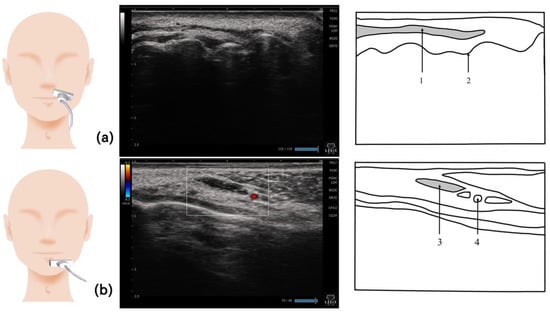

9. Orbicularis Oris Muscle (Figure 8)